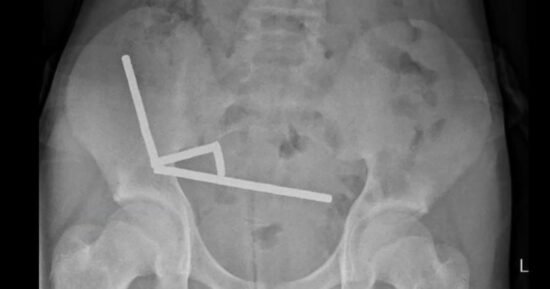

A boy who swallowed up to 100 high-powered magnets purchased online has undergone major surgery to remove them. After four days of stomach pain, the 13-year-old boy…